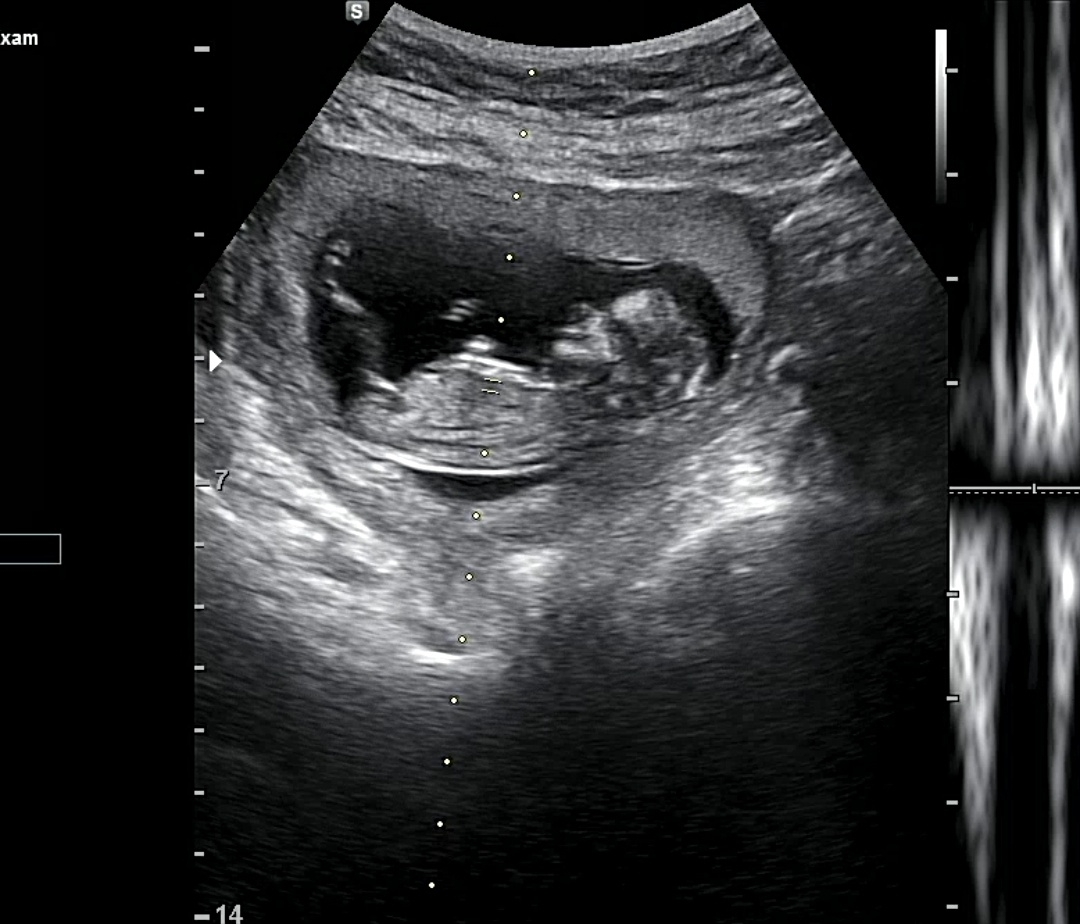

12주 각도법 봐주세요🩷